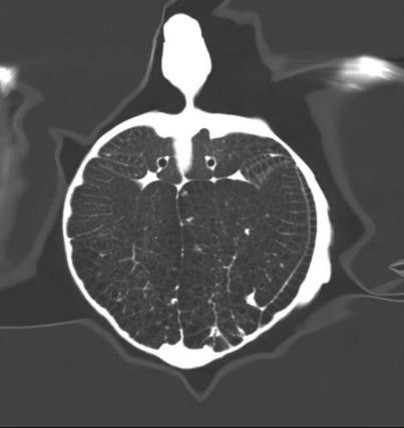

臨床畫廊